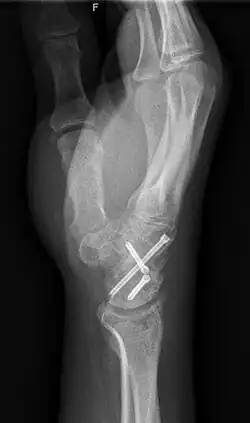

Arthrodesis is the surgical immobilization of bones within a joint to promote fusion of the joint.[20] Arthrodesis is performed most commonly on joints of the feet, hands, and spine.[21][22][23] Arthrodesis can relieve pain from arthritis and fractures.[24] This is accomplished through the use of orthobiologics such as allografts and autografts.[25] Allografts are done by creating bone grafts from a donor bone bank, whereas autografts are bone grafts from other bones in a patient's body.[25] Patient-reported outcomes following this procedure are typically positive in terms of long-term pain relief; however, the procedure also results in decreased range of motion.[26]

Arthroplasty

Arthroplasty, otherwise known as joint replacement, is a surgical procedure which involves resurfacing, realignment, or removal of bone at a joint interface to restore the joint's function.[27] Arthroplasty is often performed on hips, knees, shoulders, and ankles to improve range of motion and relieve pain from arthritis or trauma.[28][29] Arthroplasty of the shoulder is one of the most common of these procedures, although it has only been widely used since 1955.[30] Themistocles Gluck is thought to have created the first shoulder arthroplasty in the 1800s.[30] Since Gluck never published any results or notes on the procedure, Jules-Emile Pean is credited with performing the first shoulder arthroplasty in 1893.[30]